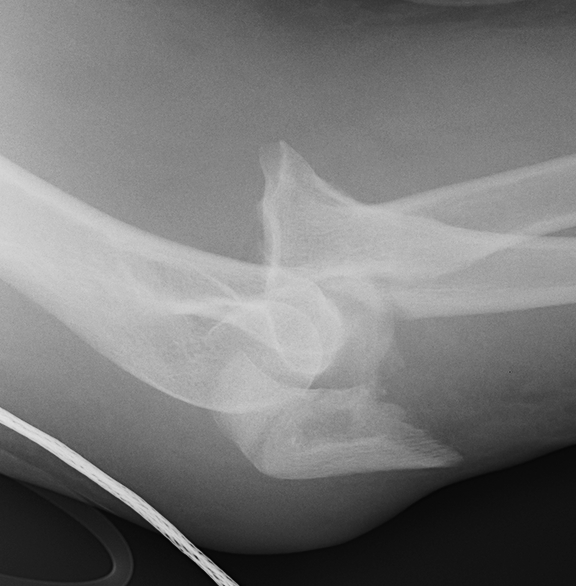

Monteggia variant

Definition

Elbow dislocation + olecranon fracture + radial head/neck fracture +/- coronoid fracture

Complex proximal ulna fracture with radial head replacement subluxation